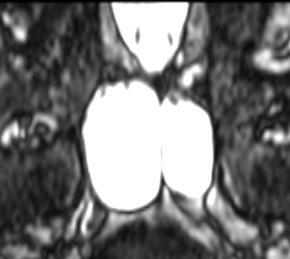

?4月10日是我特需專家門診日,D女士是第2次看我門診,我?guī)椭俅尾榭从跋駥W(xué)報告,她終于輕舒一口氣,高興地離開診室。D女士?41歲??今年3月初,她第一次來我門診時焦慮重重。她在2月中旬,與朋友們?nèi)セr不慎摔傷頭部,當(dāng)時沒有意識模糊等表現(xiàn)?;氐阶〉睾箢^痛,遂在某外地醫(yī)院做了頭CT檢查,這個CT檢查報告寫著“腦萎縮”。D女士才41歲,從小智力正常,工作狀態(tài)良好,年紀(jì)輕輕就“腦萎縮”,讓她精神壓力很大。她從線上查到我擅長各種腦外傷診療,就掛了我的特需專家號來就診,從各種臨床表現(xiàn)和她的狀態(tài)看,她并沒有問題。我仔細看了她的頭CT,發(fā)現(xiàn)她的雙額葉有兩個層面似乎有蛛網(wǎng)膜下腔間隙增寬,但腦溝回并沒有明顯增多。我覺得“腦萎縮”這個診斷依據(jù)不足。我安慰她別著急,先在我們醫(yī)院的影像科做一次復(fù)查,看看我們的影像專家如何診斷。??結(jié)果,我們醫(yī)院3月4日的頭部磁共振檢查顯示她確實有雙側(cè)額葉的蛛網(wǎng)膜下腔間隙增寬,但我們影像科專家的報告只寫了她有鼻竇炎,并無其他異常。我給她解釋:蛛網(wǎng)膜下腔間隙增寬可能是先天性結(jié)構(gòu)異常,并非疾病。就像有的人長得高大,有的人長得瘦小,只是發(fā)育成長的不同罷了。這次要不是頭部外傷后去檢查被偶然發(fā)現(xiàn),根本就發(fā)現(xiàn)不了。她又沒有癥狀,不必過度緊張,她稍微感到安慰。我考慮到蛛網(wǎng)膜下腔間隙增寬的患者,如果受到頭部沖擊,按照硬膜下血腫多發(fā)于腦結(jié)構(gòu)不對稱者的理論,應(yīng)該排除繼發(fā)硬膜下血腫的可能,囑咐她一個月后再復(fù)查一次頭MRI。??今天是她第二次來門診看她的檢查結(jié)果,而第二次換了一個影像專家,出示的報告顯示她仍然沒有“腦萎縮”(圖)。我再次跟她解釋,我們醫(yī)院的影像科是我國神經(jīng)影像的發(fā)源地,是中國第一部神經(jīng)影像著作出版地,我們的影像報告就是最終報告,不必再糾結(jié)是否“腦萎縮”。D女士這才心情寬慰,精神狀態(tài)煥然一新。離開診室前,她跟我說,近一個月來,她天天憂慮自己年紀(jì)不大就“腦萎縮”,擔(dān)心以后的生活與工作,是直到今天她才釋然……?????????????????????????????????????實際上這已經(jīng)不是第一次我和我們影像科專家背靠背地為被外院誤判為“腦萎縮”的患者解惑,但D女士的經(jīng)歷特別典型,我特別寫出來,分享給大家,希望能幫助到大眾。??由于科普不盡全面,“腦萎縮”常被當(dāng)成“老年癡呆”的代名詞,而“癡呆”所表現(xiàn)出的生活狀態(tài)和最終命運的悲慘,常引起大眾恐懼,為此,在有經(jīng)驗的影像科,從不輕易出“腦萎縮”這樣的描述性診斷。??實際上“腦萎縮”一詞出現(xiàn)在影像學(xué)報告中,既是診斷名詞,又是形態(tài)結(jié)構(gòu)的描述名詞,我的理解是,這是一個描述性診斷,未必是真的“有病”。但普通人群甚至非神經(jīng)科的醫(yī)生可沒有那么多神經(jīng)科學(xué)和醫(yī)學(xué)知識,他們往往會被這樣一個面目猥瑣的名詞給嚇暈。??而我們醫(yī)院的影像科是我們敬稱為“吳老爺子”的吳恩惠教授創(chuàng)立的,他老人家引進了中國最早的CT機,1985年就主編了我國第一部神經(jīng)影像專著:《頭部CT診斷學(xué)》,為全國培養(yǎng)了上百名著名影像學(xué)專家。經(jīng)過幾代神經(jīng)影像人的努力,我們醫(yī)院的影像學(xué)科現(xiàn)在已經(jīng)成了天津市重點學(xué)科、教育部“211工程”重點建設(shè)學(xué)科和“國家級臨床重點??啤保敲逼鋵嵉奈覈窠?jīng)影像學(xué)發(fā)祥地。也因此,我們的影像報告很權(quán)威,我也經(jīng)常請教我們的影像專家,不斷得到他們的指點。我們的神經(jīng)外科、神經(jīng)內(nèi)科之所以能夠全國知名,其中一個容易被人忽視但卻不爭的事實是,我們擁有強大的神經(jīng)影像科。因此,我們非常信賴我們的影像專家,他們也很少發(fā)出讓病人憂郁的不實診斷報告。??嗨,病友們,如果遇到讓您困惑的影像診斷,請來我們總醫(yī)院,我們的影像科非常強大!